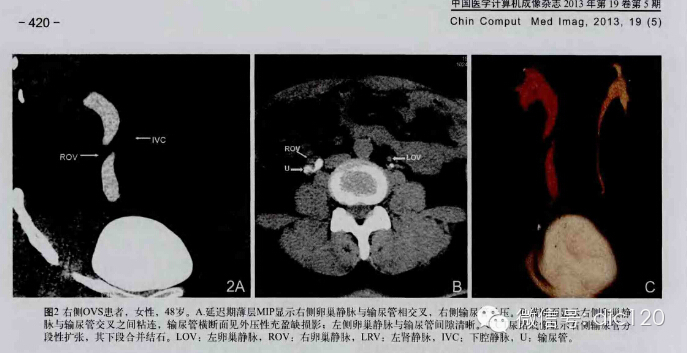

F,56Y,左腰腹部疼痛3天,B超:左肾积水,左输尿管上段扩张。

2013-8-20全麻下行“左肾盂输尿管连接部纤维束带松解 左输尿管纵切横缝术:术中沿腰大肌前方找到输尿管,将输尿管游离至肾盂处,见一纤维束带样组织压迫输尿管,将该组织松解切断,断端结扎,探查见肾盂输尿管连接处输尿管较细,于该处输尿管壁缝两针牵引线,尖刀片纵形切开输尿管壁。

结果:卵巢静脉综合征,患者有外压性输尿管梗阻,卵巢静脉与输尿管交叉处有粘连。